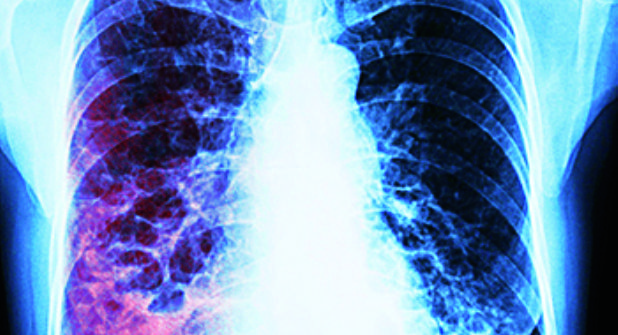

En lo que va del año, la Secretaría de Salud ha registrado 12 fallecimientos por tuberculosis, con un total de 205 nuevos casos, lo que representa un aumento del 5% más en comparación con el año 2024. Blanca Estela Morales Zapata, coordinadora del programa de Tuberculosis en la Jurisdicción Sanitaria No. 5, detalló que, entre la Secretaría de Salud y el IMSS (incluyendo IMSS Bienestar), se mantienen cifras similares, aunque ligeramente superiores al año anterior, mientras que el ISSSTE reporta menos casos.

Reiteró la necesidad de medidas preventivas, como el uso de cubrebocas en pacientes contagiosos y sus familias, especialmente tras la experiencia de la pandemia. La mayoría de los casos se concentran en personas de 25 a 45 años, principalmente hombres, con pocos menores de edad afectados. De los 205 casos registrados, 97 corresponden a la Secretaría de Salud y 107 al IMSS. Las 12 muertes ocurridas son consideradas prevenibles, dado que el tratamiento convencional está disponible y la enfermedad es curable, siempre que los pacientes sigan las indicaciones médicas.